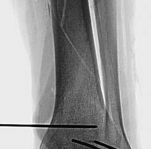

The management of complex tibial shaft fractures with extension into the distal articular surface (the tibial plafond or pilon) represents one of the most formidable challenges in orthopedic traumatology. These injuries typically result from high-energy mechanisms, such as a fall from a significant height or a motor vehicle collision, where axial loading forces are combined with severe rotational and shear vectors. The classic presentation, as highlighted in our index case of a 26-year-old male who fell 3 meters into a hole, involves not only catastrophic bony disruption but also devastating injury to the surrounding soft tissue envelope. The delicate nature of the soft tissues in the distal third of the leg, characterized by sparse muscular coverage and a precarious vascular supply, dictates the entire trajectory of clinical decision-making.

The patho-epidemiology of these injuries is inextricably linked to the incidence of acute compartment syndrome. High-energy axial loads result in rapid swelling, hemorrhage, and edema within the unyielding fascial compartments of the leg. As demonstrated in our reference case, clinical examination often reveals a tense, swollen limb necessitating an immediate four-compartment fasciotomy. The dual-incision technique remains the standard of care to decompress the anterior, lateral, superficial posterior, and deep posterior compartments. The presence of fasciotomy wounds further complicates the surgical approach for definitive internal fixation, requiring strict adherence to the principles of damage control orthopedics (DCO).

Image

Initial management in these high-velocity scenarios mandates the application of a spanning external fixator to achieve skeletal traction, restore length, and allow the soft tissue envelope to recover. This temporary stabilization minimizes ongoing secondary soft tissue trauma from mobile fracture fragments. However, the application of external fixators is not without risk; meticulous pin placement is required. For instance, calcaneal transfixion pins must be placed with strict attention to the neurovascular bundle to avoid iatrogenic tibial nerve irritation, an issue that required revision in the early phase of our index patient's care.